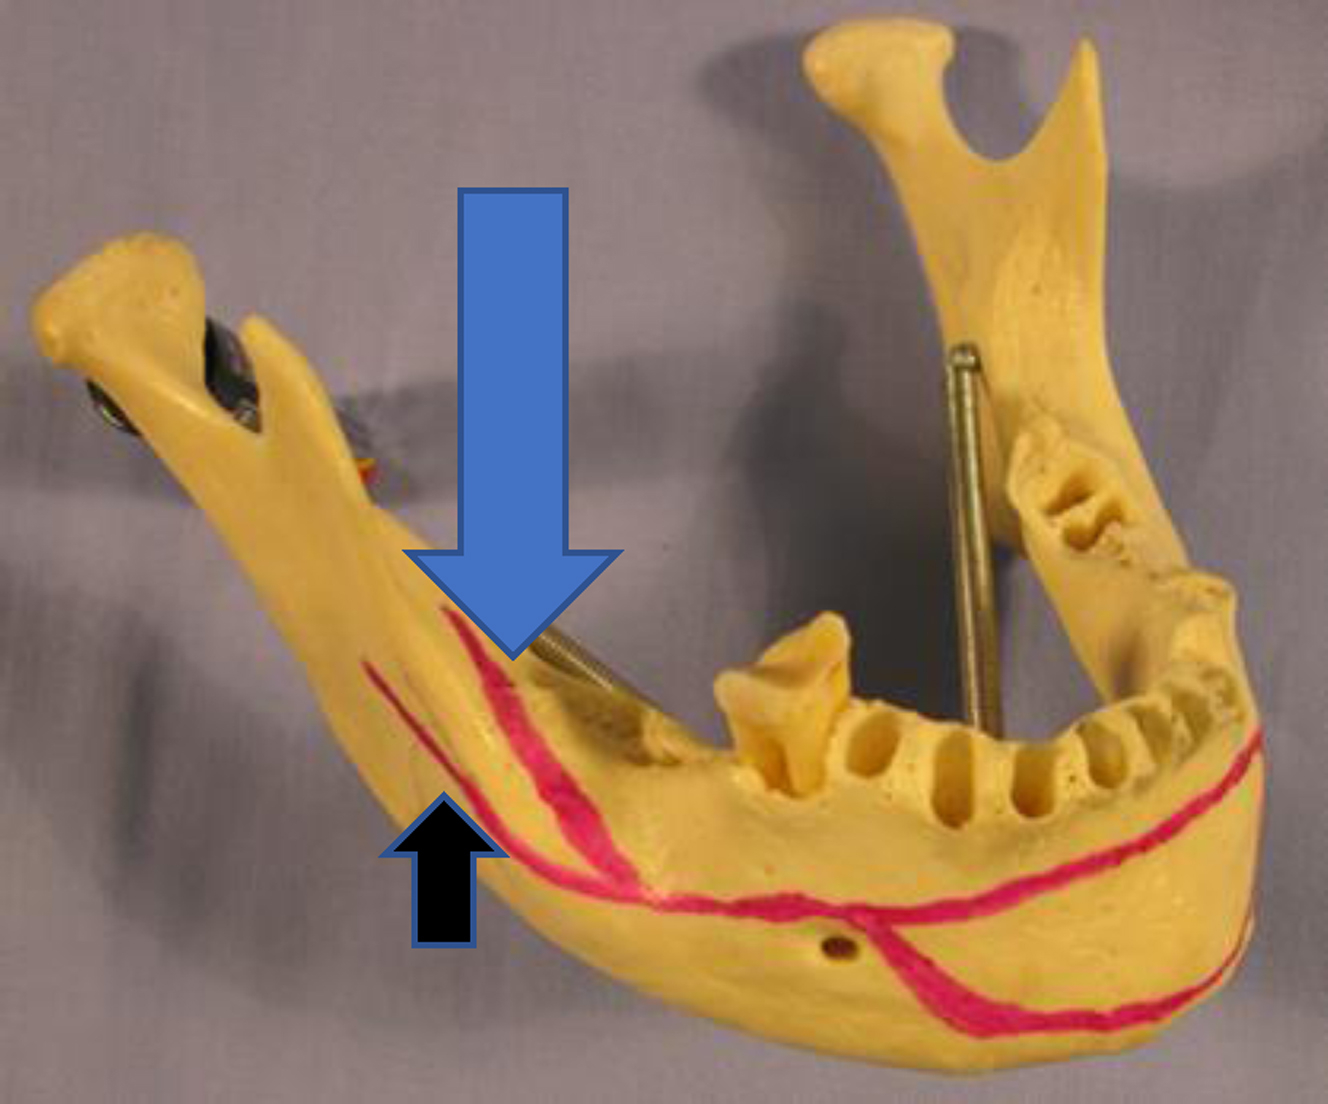

Currently, the Champy technique for osteosynthesis is used preferentially for noncomminuted fractures of the mandibular angle. The Champy technique was popularized by Maxime Champy in the 1970s. Dr. Champy recognized that the angle of the mandible had certain characteristics that were favorable with regard to using a load-sharing engineering concept with regard to mandibular fixation. Load sharing is an engineering technique where forces caused by mandibular function will be counteracted by placing plates with monocortical screws in such a way that tensile or distractive forces are obviated while beneficial compressive forces are strategically promoted. This is in contrast to load-bearing repairs, whereby all forces at play on a functioning mandible will be overcome and neutralized by thick and rigid plates that have absolutely no mobility and use bicortical screw placement. The Champy technique uses optimal plate placement along Champy’s lines using monocortical screws that counteract tensile forces that occur during mandible function while allowing compressive forces to be controlled in the pursuit of bone healing ( Fig. 2 ). By using monocortical miniplates to counteract tensile forces, smaller and thinner plates can be used. Less surgical exposure and periosteum stripping is required, and less bone drilling is necessary. However, the Champy technique is not a rigid technique. It does allow some movement at the fracture site after repair. The Champy technique also relies on bone surface area contact to help stabilize the fracture, and therefore, comminuted fractures are not ideal for the technique ( Fig. 3 ). One other factor makes the angle an opportune place for utilization of this technique: the fact that angle fractures are actually behind the dentate portion of the mandible. Similar to sagittal split osteotomy surgery, the location of the angle fracture in this retro-occlusal zone allows leeway with regard to the precision of the final osteosynthesis as it relates to postoperative occlusion.

There have been numerous studies investigating the use of one versus two monocortical miniplates in open reduction and internal fixation of MAFs. Historically Michelet and colleagues, and later Champy and colleagues, introduced of the use of a single miniplate on the superior lateral border of the mandibular angle for osteosynthesis in MAFs ( Fig. 4 ). However, given the tensile forces of elevation on the mandibular ramus countered by the depressor forces on the mandibular body, later studies theorized that two miniplates should be placed, one superior and one inferior across the MAF ( Fig. 5 ). This has not been borne out in the literature as studies in which two points of fixation were used had higher complication rates than studies in which one miniplate was used. , A 2014 systematic review and meta-analysis by Al-Moraissi and Ellis found the use of one miniplate to be superior to the use of two, reducing postoperative complications (including dehiscence, infection, nonunion, malunion, malocclusion, and hardware failure). This corroborated randomized control trials of the same topic, showing that the use of two miniplates for MAF gave no additional benefit and increased both procedure time and risk of postoperative complication.